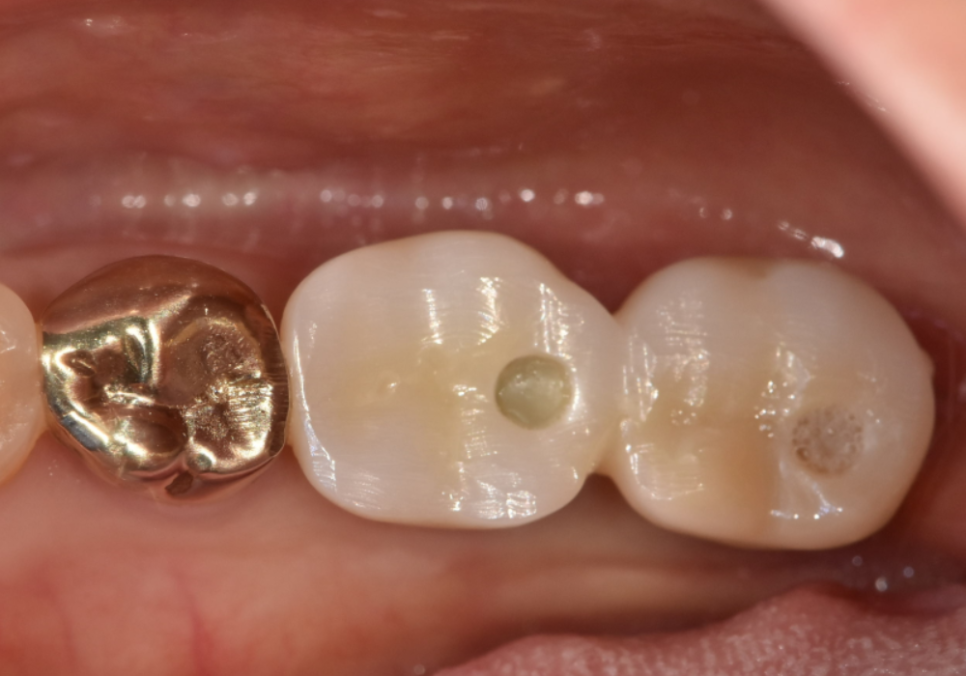

토대가 완벽하게 만들어진 것을 확인한 후,

기존에 두 임플란트를 하나로 묶고 있던

낡은 보철물을 제거하고

241223

강도와 심미성이 뛰어난

지르코니아 보철물을 새롭게 제작해 드려

치료를 마무리했습니다.